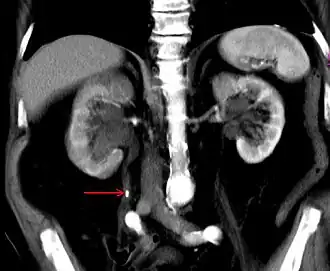

Diagnostik

- CT, zeigt auch die sogenannten nicht schattengebenden Konkremente, die in konventionellen Röntgenaufnahmen nicht zu sehen sind